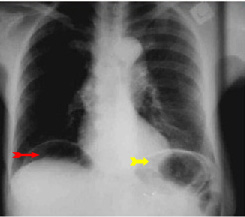

בצילום חזה ניתן לראות אוויר חופשי מתחת לסרעפות (תצלום 6.3). בבליעת בריום ניתן לראות דלף של חומר מחוץ לקיבה אם ההתנקבות היא אחור-צפקית (תצלום 7.3).